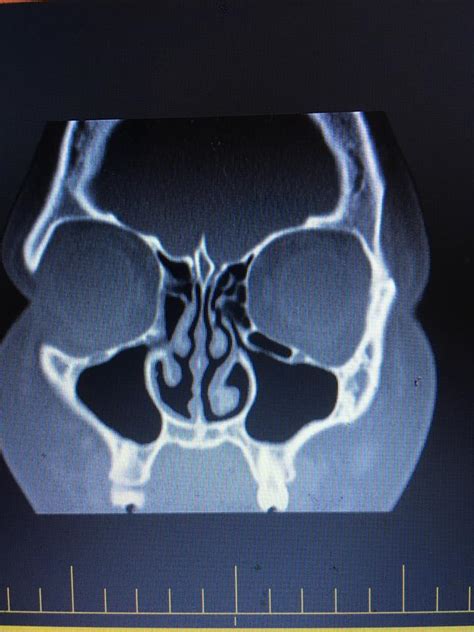

Okay, so why a CT scan and not just, say, a regular X-ray? Well, CT scans (computed tomography scans) give doctors a much more detailed look inside your body. Think of it like a super-powered X-ray. Instead of just one flat image, a CT scan takes multiple X-ray images from different angles and combines them to create cross-sectional views – like slices – of your sinuses. This allows the radiologist to see everything clearly. They can show the extent of the inflammation, see if there’s any fluid buildup (which is a big sign of infection), and even spot things like nasal polyps or structural problems that might be contributing to the issue. A CT scan is typically ordered when a doctor suspects that a patient has a chronic or severe sinus infection. This is because a CT scan is able to show fine details about the sinuses and surrounding tissues. If a person has a mild sinus infection, their doctor will most likely treat it by treating the symptoms. Sinusitis symptoms include: facial pain, a stuffy nose, congestion, headache, fever, cough, fatigue, and a reduced sense of smell. So, what do they look for on a CT scan ? Doctors will be looking at how inflamed the tissues are, if there are any blockages, and if there is a fluid build-up. The radiologist will be able to tell what may be causing your sinus infection, such as a bacteria or allergies. A CT scan of the sinuses can also detect complications such as orbital cellulitis (an infection of the tissues around the eye), meningitis (an infection of the membranes surrounding the brain and spinal cord), or a brain abscess. These complications are rare, but can be very dangerous.

What the CT Scan Reveals: Key Findings and Interpretations

So, what exactly are doctors looking for when they read a sinus CT scan ? The scan can reveal a variety of things, including:

- Inflammation: The most common finding is inflammation of the sinus lining. This looks like a thickening of the tissues within the sinuses.

- Fluid Buildup: This is a sign of infection and can appear as a dark area within the sinuses.

- Blockages: The scan can show if the sinus openings are blocked by swelling, mucus, or other obstructions.

- Nasal Polyps: These are small, noncancerous growths that can develop in the nasal passages or sinuses. The CT scan can help identify them.

- Structural Abnormalities: The scan can reveal any issues with the structure of your sinuses, such as a deviated septum (when the wall between your nostrils is shifted to one side). This can be a factor contributing to frequent sinus infections. The radiologist interprets these findings and provides a detailed report to your doctor. The report will describe what they see in the images and help the doctor make an accurate diagnosis and create a treatment plan. The doctor will most likely recommend treatments based on the results from the CT scan .